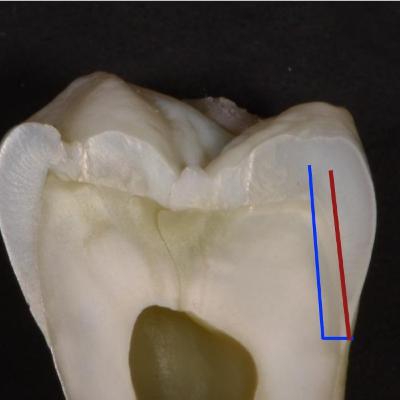

© Dr. Hadi Horri DDS

Compact and brief description of new and rather more practical techniques and ideas in the field Dentistry . This podcast is in Persian (Farsi) language .